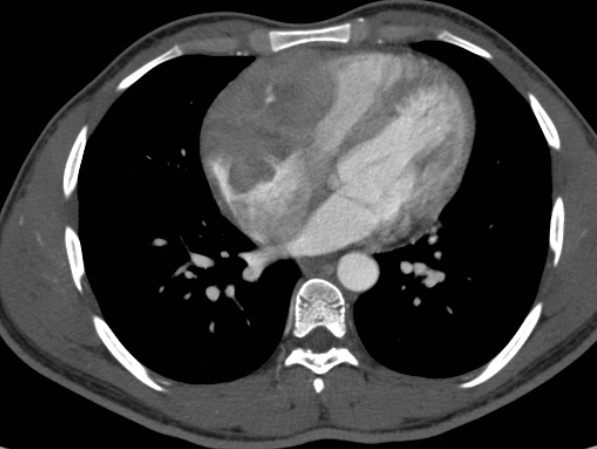

La tomografia computerizzata (TC) total body con contrasto mostrava all'interno del cuore destro una massa ipodensa, solida, che infiltrava le pareti del miocardio (Figura 2), circondava la radice aortica e confluiva nel mediastino superiore in una massa di linfonodi patologici fusi (Figura 3). Per il resto, la TC total body non dimostrava altri siti patologici.

linfoma_cardiaco_2.jpg

Figura 3

La TC permetteva di confermare la malignità della massa, sulla base della sua infiltrazione miocardica e pericardica. Nella fase post-contrasto una scarsa vascolarizzazione del tumore rappresentava una differenza significativa rispetto al tessuto riccamente vascolarizzato dell'angiosarcoma (che è il più frequente tumore cardiaco maligno). Inoltre, la TC evidenziava che il tumore cardiaco continuava nel mediastino superiore in una massa uniforme di linfonodi patologici con lo stesso pattern di segnale. Questo riscontro suggeriva la diagnosi di linfoma. D'altra parte, la mancanza di altre metastasi escludeva la diagnosi di angiosarcoma e di sarcomi in generale.